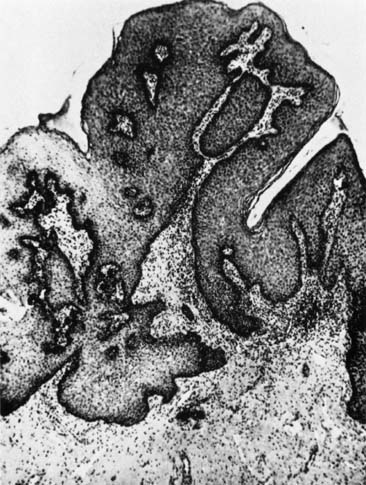

Papillomas that are not HPV-related can occur in the cervix and usually originate from the exocervix near the squamocolumnar junction (transformation zone). These are thought to be related to local irritation or scarring and are usually less than 1 cm. Their natural history is not well described, as the usual intervention for these papillomas is excision to assure that this does not represent malignancy1 (Figs. 5 and 6).

Fig. 5. Squamous papilloma of the cervix.

Fig. 6. Benign squamous papilloma of the cervix.